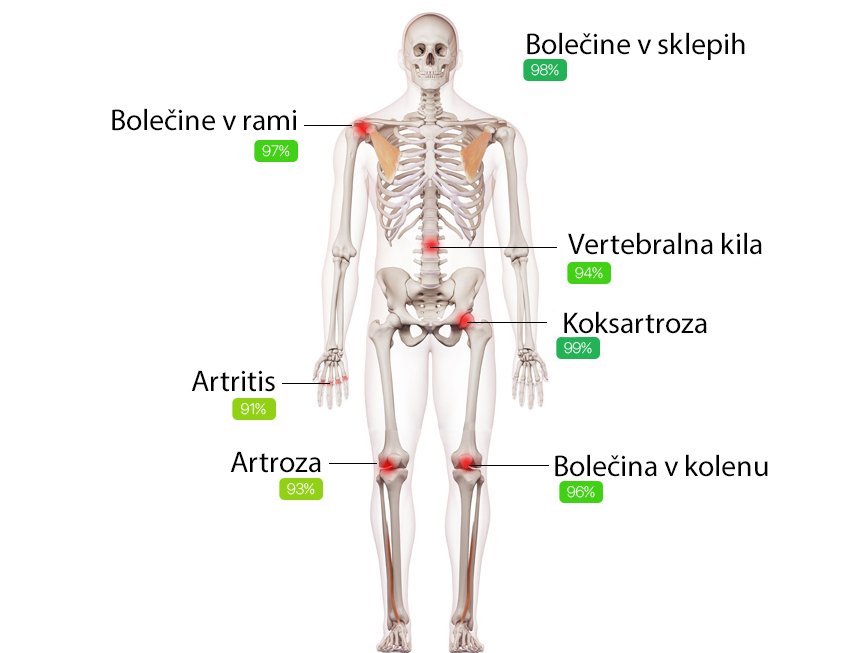

HondroLife rešuje večino znanih težav s sklepih

82% učinkovitost

Na skupno količino težav

s sklepi in mišično-skeletnim sistemom